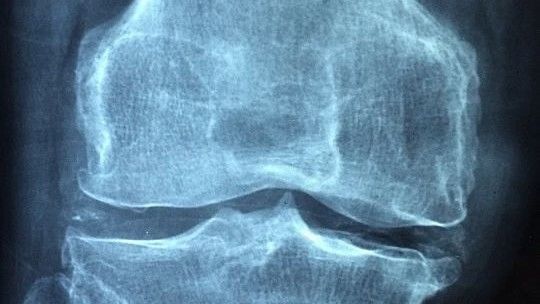

补钙能起到多大的作用?

骨质疏松的病因很多,首先需要找到确切的病因,对因治疗才可以,不可盲目补钙,更不能认为“补钙就能治好骨质疏松”。

补钙是基础治疗,也就是无论辅助其他治疗,都需要补充钙剂,而且补钙是一个长期的过程。但钙只是应对骨质疏松的一种“原材料”,就好像盖房子需要砖块、沙子、水泥、钢筋等很多种材料,而且要组合好才行,单纯补钙肯定达不到治疗骨质疏松的目的。另外,补充到人体的钙剂无法直接聚集在骨骼,只是让骨骼里的钙不再流失,而维生素D以及治疗骨质疏松的一些药物,则可以增加骨密度,降低骨折风险。因此,要想防治骨质疏松,调整饮食、合理用药、坚持锻炼、做好防护,这些措施都要有。